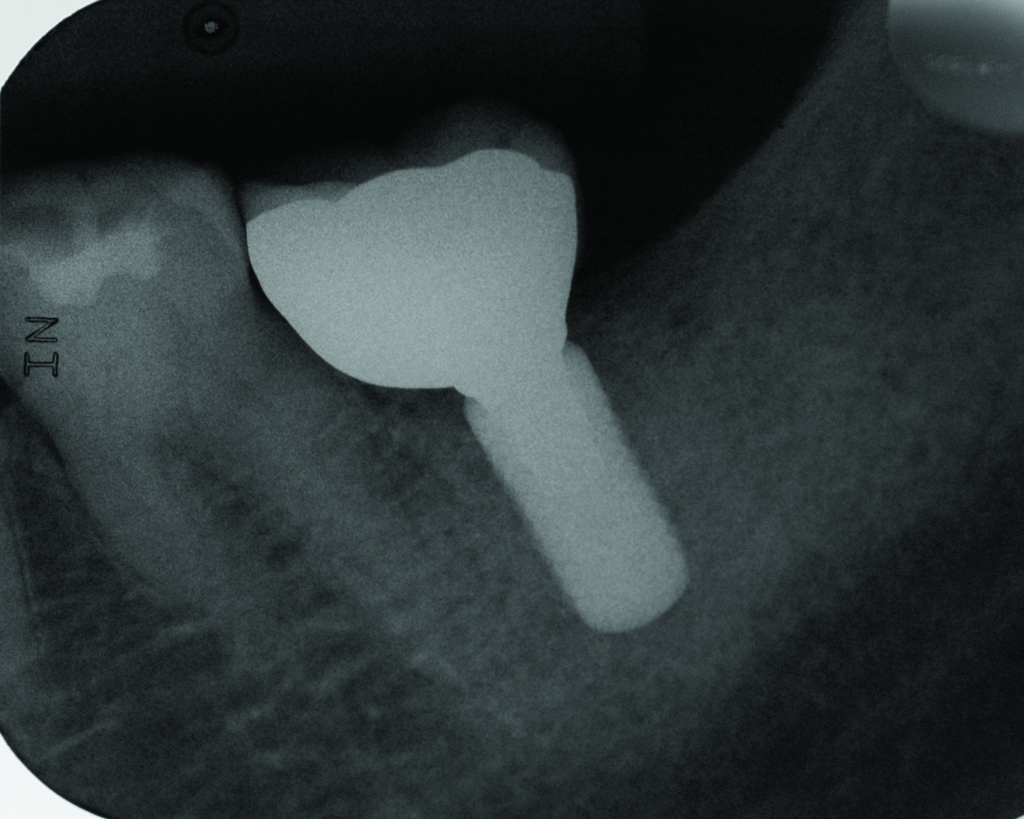

Clinical view of a maxillary left second premolar in an 73-year-old patient with a history of smoking. The tissue around the implant is quite inflamed and probes up to 8 mm with bleeding.

Figure 3

Radiograph of the area suggests moderate to advanced bone loss at the mesial aspect making the diagnosis peri-implantitis.

Figure 4